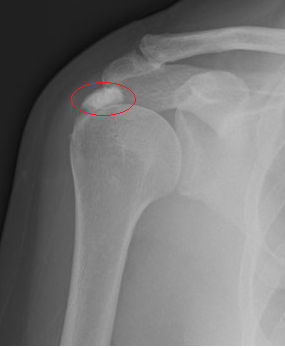

Η «Ασβεστοποιός Τενοντίτιδα» του ώμου είναι η συγκέντρωση και εναπόθεση ασβεστίου μέσα στους τένοντες του ώμου. Πρόκειται για μια τενοντίτιδα που προκαλεί περισσότερα ενοχλήματα από την απλή τενοντίτιδα. Mερικές φορές ο πόνος είναι εξαιρετικά έντονος. Άλλοτε ο ασθενής έχει ιστορικό ενοχλήσεων στον ώμο ενώ άλλοτε μπορεί να εμφανιστεί ξαφνικά.

Εικ. απεικόνιση και ακτινογραφία ασβεστοποιού τενοντίτιδας